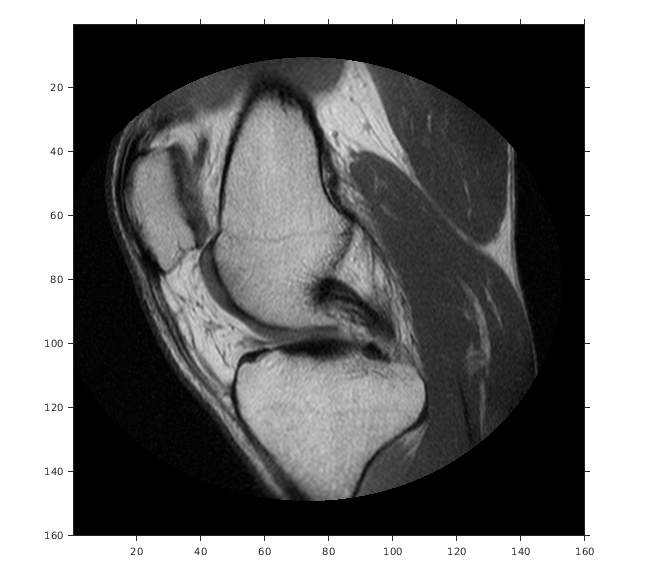

Считайте 2D полутоновое изображение колена в рабочую область.

m = dicominfo('knee1.dcm');

A = dicomread(m);

Создайте imref2d объект, задавая размер и разрешение пикселей. Файл DICOM содержит поле метаданных PixelSpacing это задает разрешение изображения в каждой размерности в миллиметрах на пиксель.

RA = imref2d(size(A),m.PixelSpacing(2),m.PixelSpacing(1))

Отобразите изображение, включая пространственный объект привязки. Координаты осей отражают мировые координаты. Заметьте, что координата (0,0) находится в левом верхнем углу.

figure

imshow(A,RA,'DisplayRange',[0 512])